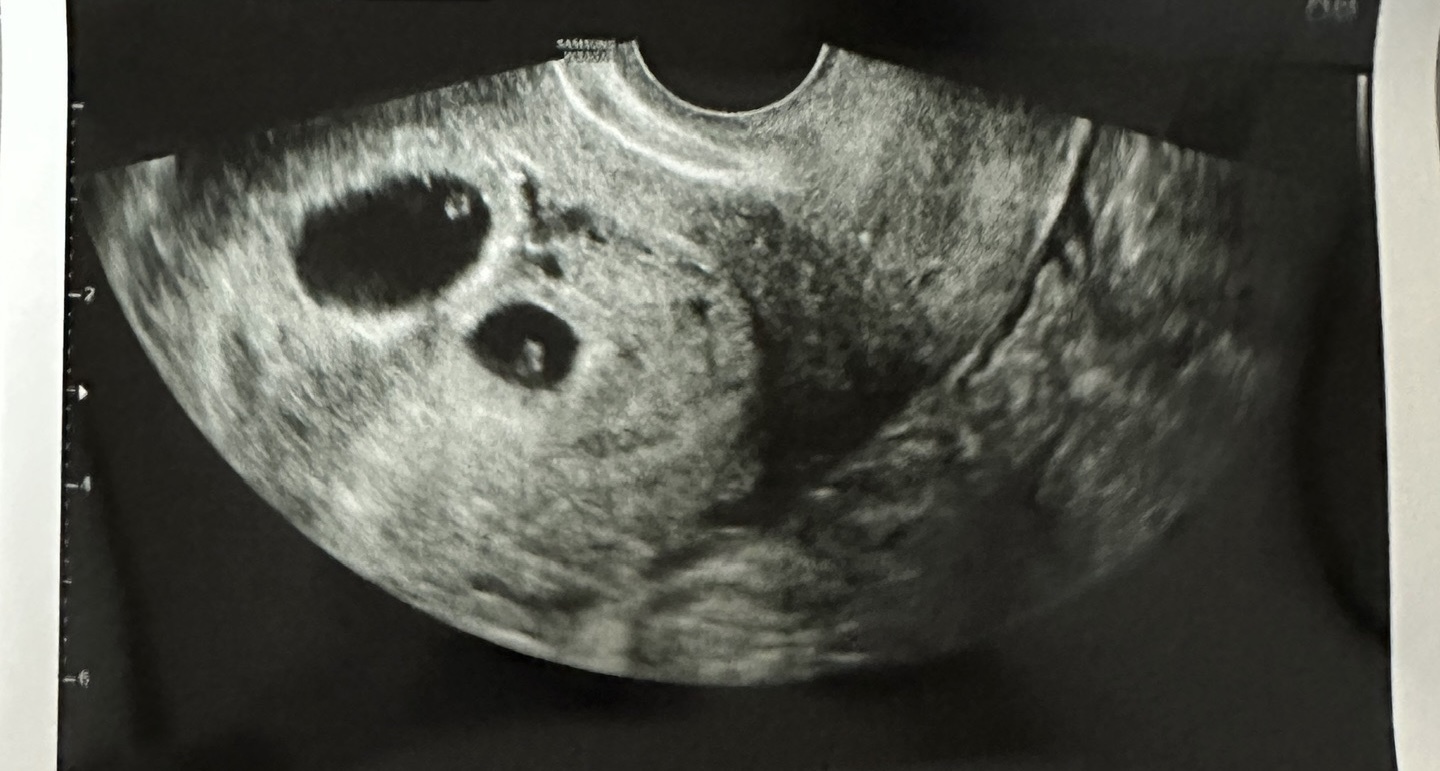

저는 현재 자녀 한 명을 키우고 있는데요. 제가 둘째를!!! 아니 셋째를!!! 임신했어요 ...ㅎㅎㅎ 🫢🫢

더 놀라운 사실은 쌍둥이를 임신했다는 사실! ... 정말 생각하지도 못한 일이었기에 너무 놀랐고 막막했는데,

지금은 마음을 잘 추스르고 아이들이 건강하게만 잘 태어날 수 있도록 기쁜 마음으로 기다리고 있습니다.